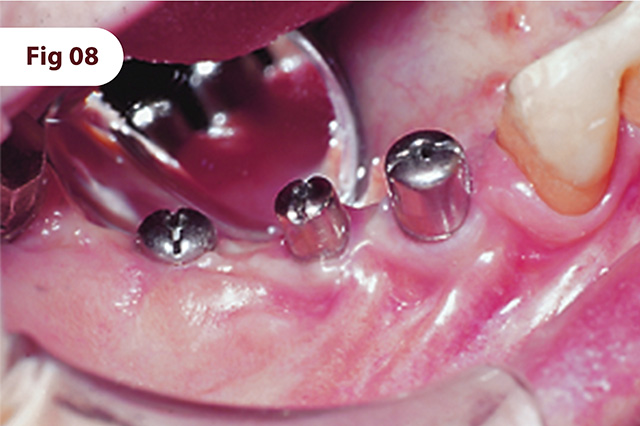

Implantes instalados no osso regenerado.

A reabertura foi feita 6 meses após a instalação. Mucosa periimplantar saudável, 30 dias após a instalação dos cicatrizadores.